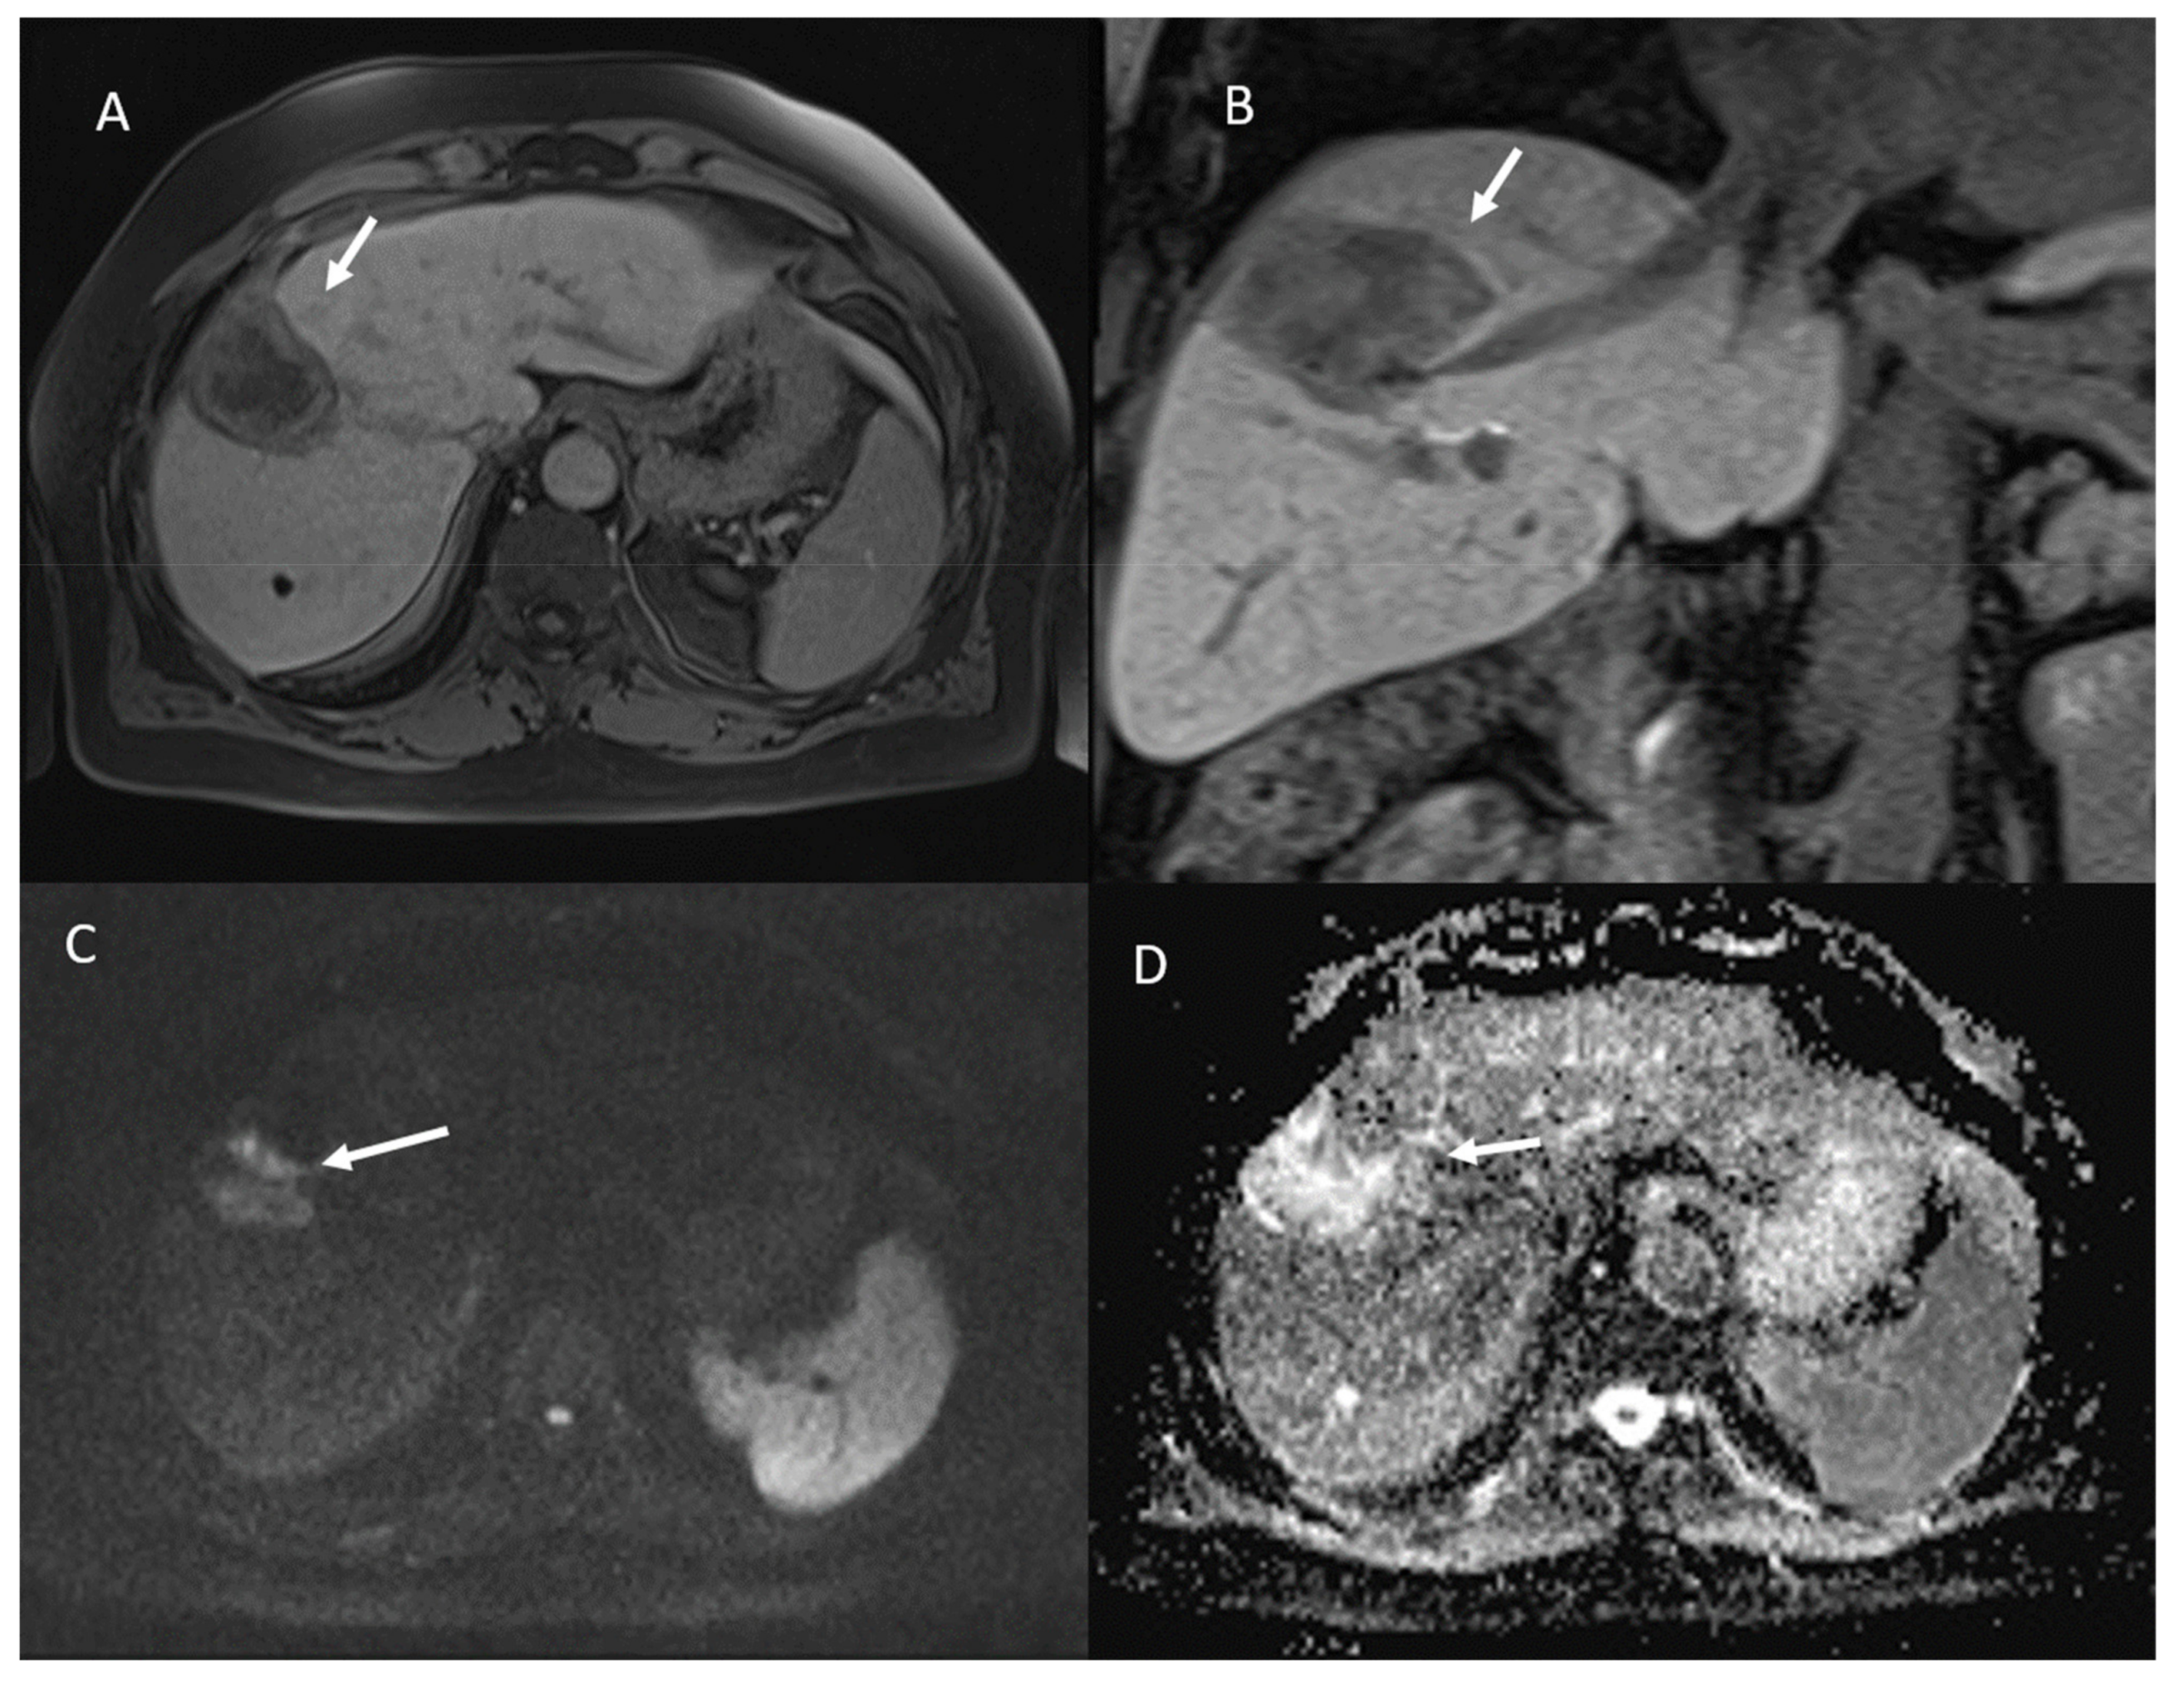

- 23 lesions showed restricted diffusion with hypointense SI in ADC map (Figure 4).

- 84 lesions showed restricted diffusion (Figure 7) with iso-hypointense in ADC map and 29 showed no restricted diffusion.